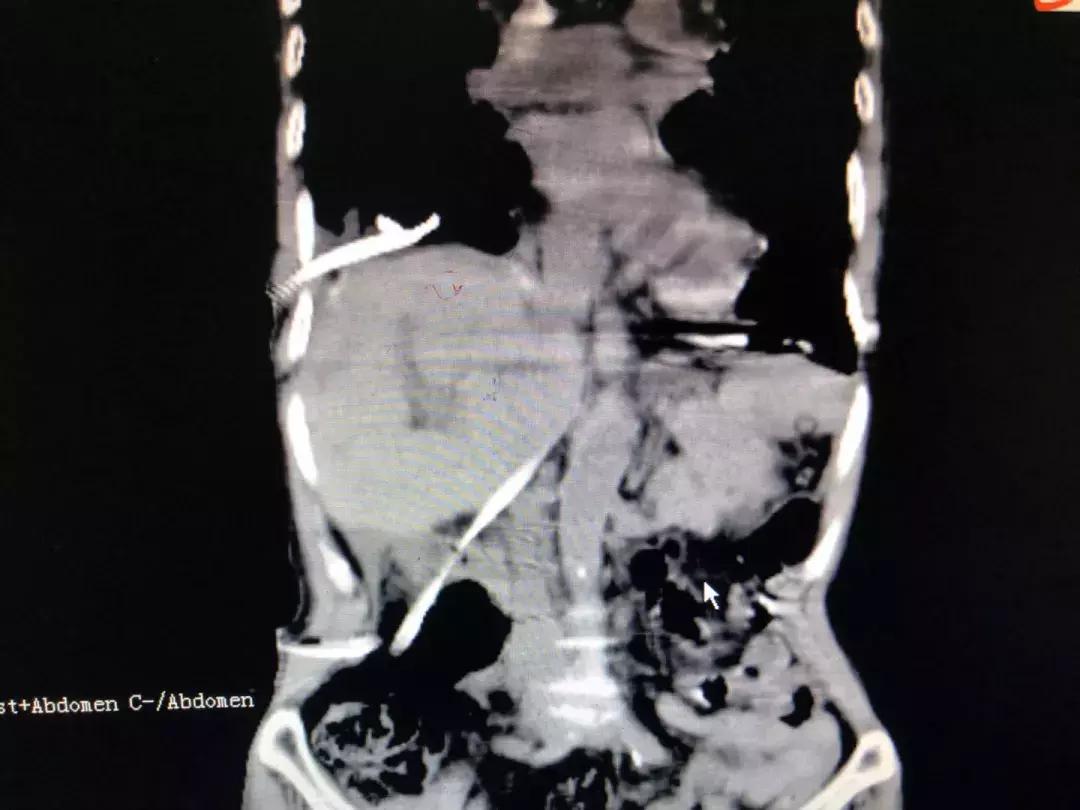

右侧膈肌缺如,部分腹腔脏器上移至胸腔内。

术后,移位至胸腔的腹腔脏器回归原位。

12月29日,在充分的术前讨论制定周密的手术方案后,手术如期举行。吴金术、汪新天、何自力等肝胆外科专家与心胸外科周文武主任医师一道洗手上台。麻醉后,患者心率一度高达130,血压74/33mmHg。经过胆道减压后,心率、血压稳定,探查发现:右膈肌缺如,肝脏、胆囊、横结肠都疝入胸腔。

周文武主任医师为患者施行膈下修补后,再由肝胆外科专家进行肝门胆管整形和取石操作。手术过程顺利,患者术后恢复良好,没有出现腹腔、胸腔感染和积液,右肺扩张良好,胆道通畅,于2019年1月18日顺利出院。